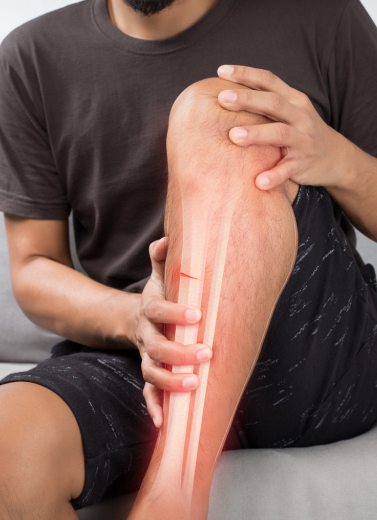

We Treat All Types of Bone Injuries and Trauma Cases

Complex & Comminuted Fractures

Accident or Road Injury-related Trauma